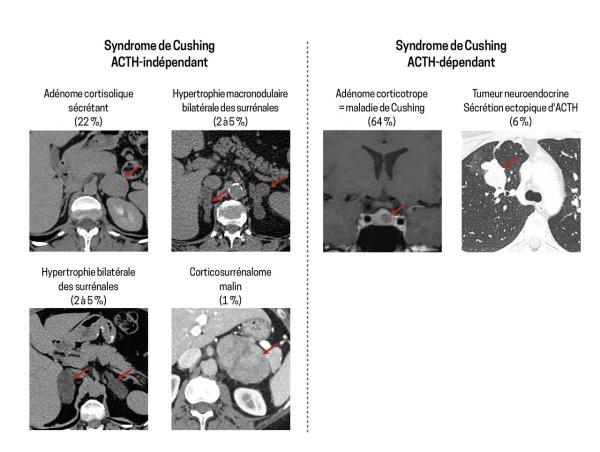

Causes du syndrome de Cushing et leur prévalence

Figure 3.

Extrait de : Syndrome de Cushing

Syndrome de Cushing